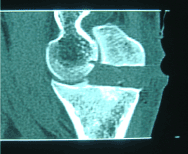

Mr Z, 30 years old , right handed consulted for an 18 months history of spontaneously occuring pain in his right elbow. It was inflammatory type, permanent and resistant to analgesic drugs (paracetamol). The pain was located at the outer side of the elbow and was radiating to the dorsal side of the forearm. He has had multiple epicondyle injections without efficiency in pain relief . Clinical examination revealed a sharp pain caused by lateral epicondyle palpation, painful mobility of the elbow with a flessum of 20 °, whereas pronosupination was normal . X-rays investigation was normal (Fig 1 and 2), biology and electromyogram (EMG) were abnormal. Ultrasonography of the right elbow showed significant synovial thickening with color doppler hyperhemia associated with intra-articular effusion. Scintigraphy showed diffuse hyperfixation of the elbow. MRI showed significant bone and of soft tissue oedema associated with joint effusion. The CT revealed a calcified nidus of the large sigmoid cavity of the ulna surrounded by a clear border within a poorly limited osteocondensation with intra-articular effusion (Fig. 3). The diagnosis of intra-articular osteoid osteoma of the elbow was confirmed and the aspirin test was positive. Because of the difficulty of the surgical approach, percutaneous resection was used under CT guidance. Loco-regional anaesthesia (axillary block) following the classic aseptic rules was done. A guide pin was placed posterolaterally after CT scan and then using a motorized 8mm diameter trephine, a block resection of the osteoid osteoma was performed. The CT control confirmed the complete resection of the nidus (Fig.4). A postoperative immobilization of seven days has been prescribed. The evolution was marked by a complete and immediate disappearance of the pain and a recovery of the elbow mobility. Histological examination confirmed the diagnosis of osteoid osteoma. Thirteen months after surgery, the elbow was painless, with complete mobility, and radiological control showed the ossification of the resected bone core.

Fig 4: CT control confirmed the complete resection of the nidus